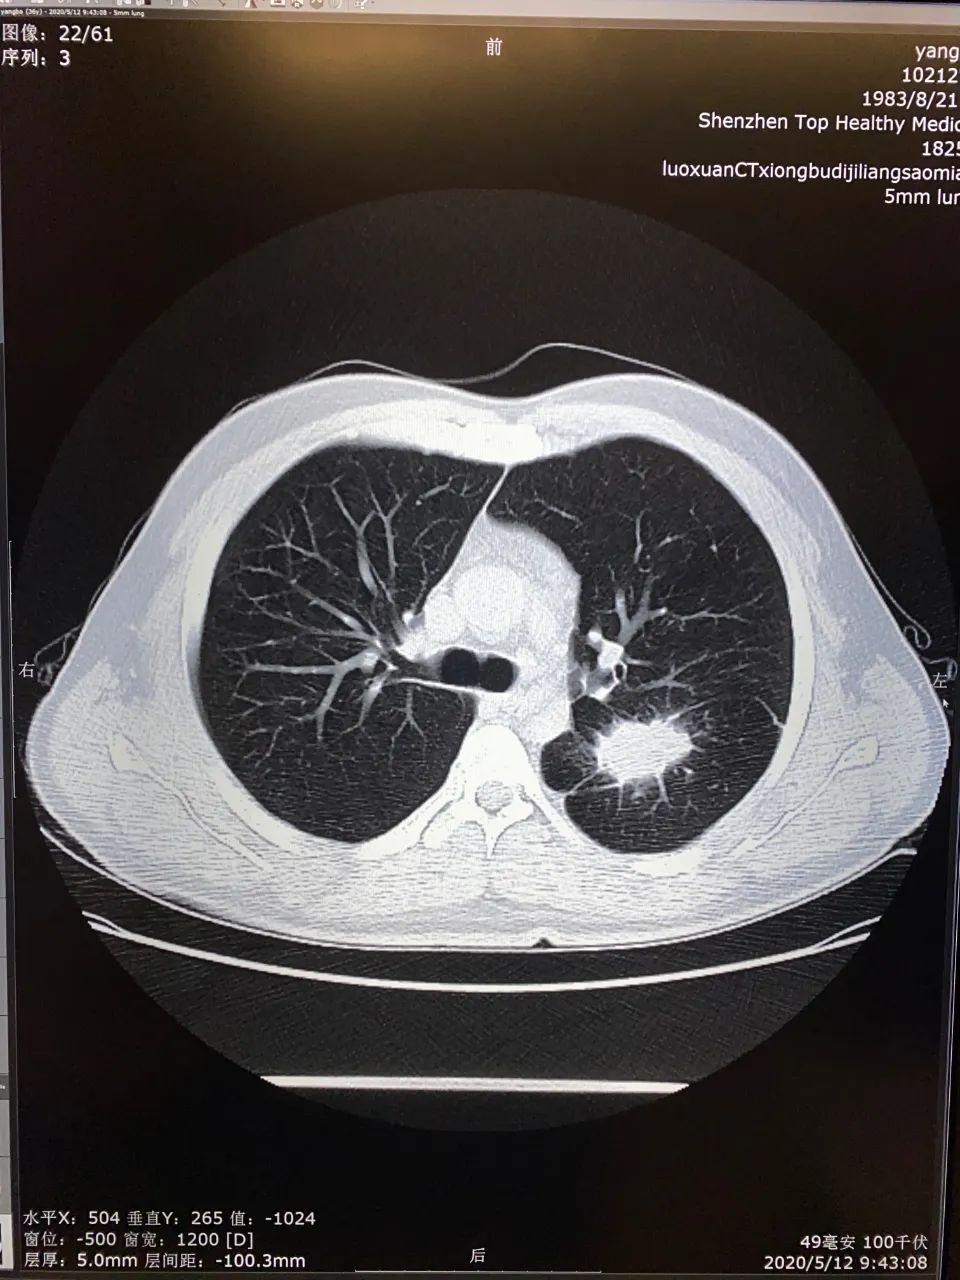

杨先生和臧主任缘起第一健康的一次体检。今年5月,杨先生来到第一健康进行体检。其中螺旋ct胸部低剂量扫描结果显示,杨先生左肺下叶背段出现了占位性病变——有恶性征象的“蜘蛛样”肺肿块。